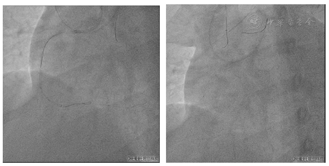

患者无法提供外院冠状动脉造影影像,于2022年6月17日我院行冠状动脉造影提示右冠状动脉中远段完全闭塞,回旋支重度狭窄,前降支轻度狭窄(图3)。

患者存在劳力性胸闷、气促症状,心脏超声未提示下壁节段性室壁运动分析异常,左心室明显扩大,LVEF减低,无室壁瘤,右冠状动脉中远段CTO,J-CTO评分4(钝头,造影未见钙化,>20 mm,成角>45°,有既往LAD-PCI失败史)。考虑右冠状动脉PCI难度大,需要考虑逆向介入可能,决定择期行RCA-CTO介入治疗,造影同期处理回旋支病变(图4)。